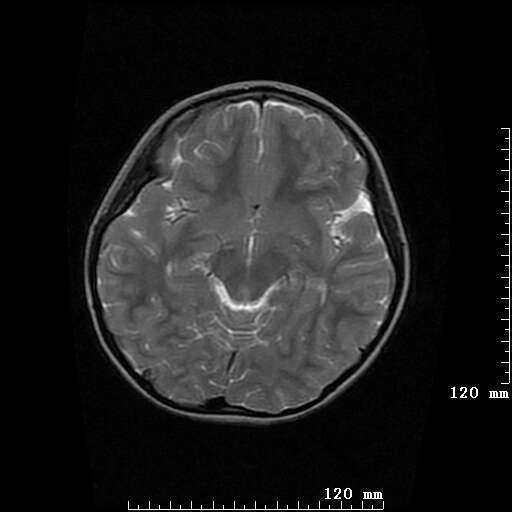

女,7岁,三岁才说话、走路。现智力尚可,走路不稳。临床怀疑大脑发育不全。

考虑 脑白质发育不良

脑折质变薄,双侧侧脑室稍扩张,支持考虑脑折质发育不良

侧脑室周围白质软化症。

考虑胼胝体发育不全,髓鞘形成不良。

支持考虑胼胝体发育不全,髓鞘形成不良。

脑裂畸形伴灰质异位

侧脑室周围白质数量减少,侧脑室不对称性扩大,左侧侧脑室后角呈方形改变,脑沟加深,结合临床考虑脑室周围白质软化症(pvl)。期待结果!

只看出灰质异位

支持脑白质发育不良。